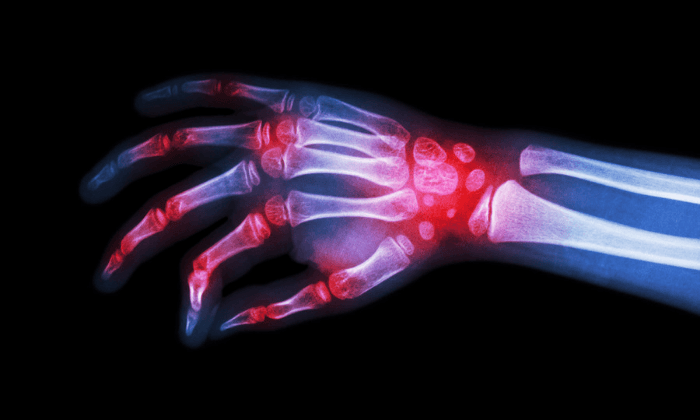

ข้ออักเสบรูมาตอยด์ (Rheumatoid arthritis) เป็นโรคเกี่ยวกับการอักเสบเรื้อรังที่สามารถส่งผลมากกว่าเพียงข้อต่อ ในผู้ป่วยบางราย ภาวะนี้สามารถสร้างความเสียหายแก่ระบบร่างกายได้มากมาย เช่น ผิวหนัง ดวงตา ปอด หัวใจ หลอดเลือด

ข้ออักเสบรูมาตอยด์ (rheumatoid arthritis) จัดเป็นโรคภูมิต้านเนื้อเยื่อของตนเอง หรือโรคภูมิต้านตนเอง หรือโรคภูมิแพ้ตัวเอง (autoimmune disorder) เกิดขึ้นเมื่อระบบภูมิคุ้มกันต้านเนื่อเยื่อในร่างกายของคุณ เนื่องจากเข้าใจผิดว่าเป็นสิ่งแปลกปลอม ข้ออักเสบรูมาตอยด์แตกต่างจากความเสียหายที่เกิดจากการเสื่อมของข้อเสื่อม (osteoarthritis)

เนื่องจากข้ออักเสบรูมาตอยด์นั้นส่งผลต่อแนวเนื้อเยื่อข้อต่อ ทำให้เกิดอาการปวดบวม ที่ค่อยๆ ทำให้เกิดกระดูกผุ (bone erosion) และข้อต่อผิดรูป (joint deformity)

ข้ออักเสบรูมาตอยด์เกิดขึ้นเมื่อระบบภูมิคุ้มกันของคุณต้านไขข้อ (synovium) ซึ่งเป็นแนวเยื่อที่ล้อมรอบข้อต่อ การอักเสบที่เกิดขึ้นทำให้ไขข้อหนาขึ้น ซึ่งในท้ายที่สุดสามารถทำลายกระดูกอ่อน และกระดูกภายในข้อต่อได้ เมื่อเส้นเอ็นที่ยึดข้อต่อเข้าด้วยกันอ่อนแอลงและยืดตัวออก ข้อต่อจะค่อยๆ สูญเสียรูปร่างและการวางแนว